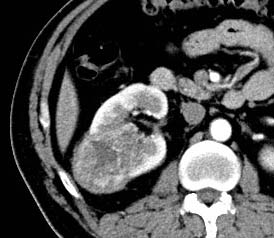

But, when we analyzed the degree of enhancement (hyperdensity, isodensity, hypodensity) in arterial (corticomedullary) and venous (nephrographic) phases showed significant difference. In arterial phase, most of clear cell RCC (21 of 39, 53.8%) showed hyperdensity, whereas none of non -ccRCC (0 of 22,0%) showed hyperdensity. The P value was 0 (P<0.05). In venous phase, ccRCC showed more hyperdensity or isodensity (9 and 4 0f 39, 23.1% and 10.3% respectively) than non-ccRCC (0 and 1 of 22, 0% and 4.5% respectively). Almost all of the non-clear cell RCC ( 21 However, we did not get any significant difference, when compared degree of enhancement in delayed phase (excretory phase). Table 3: shows the comparison of degree of enhancement in different phases in between ccRCC and non-ccRCC. The pattern of enhancement (homogeneous or heterogeneous) showed significant difference. Nonclear cell carcinoma (19 of 22, 86%) showed more heterogeneous enhancement pattern than that of clear cell carcinoma (21 of 39,53%). The P value was 0.012 (p<0.05).

However, when we compared pattern of enhancement, most of clear cell RCC (53.5%) showed heterogeneity, which agree with other studies related with pattern of enhancement of ccRCC [8,10]. But, when we made comparison of heterogeneity in between ccRCC and non-ccRCC, we found that, non-ccRCC were more heterogeneous than ccRCC. This may be because of larger size of non-ccRCC S which tended to show heterogeneity due to propensity of hemorrhage, necrosis and calcification [24][25][26]. At microscopic examination, all tumors with homogeneous enhancement were mainly composed of solid elements, whereas all tumors with heterogeneous enhancement had solid elements, necrosis, hemorrhage and calcifications.

Calcification is more common in non-clear cell RCC 27% (6 of 22) than clear cell RCC 7% (3 of 39).The p value was significant (p=0.038). In our study, we also made comparison in between non-clear cell RCC and clear cell RCC with hypovascular tumor. We found significant p values when we compared size, location, pattern of enhancement and presence or absence of necrosis in between these two types.